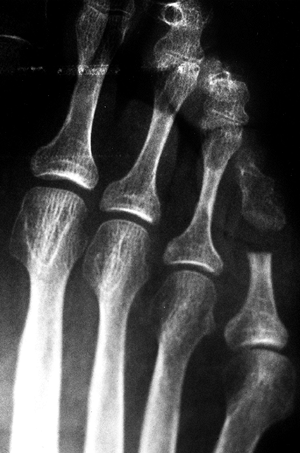

Figure 113.6. A: A hard hyperkeratotic region over the PIP joint of the fifth toe. B: The radiograph of the toe.